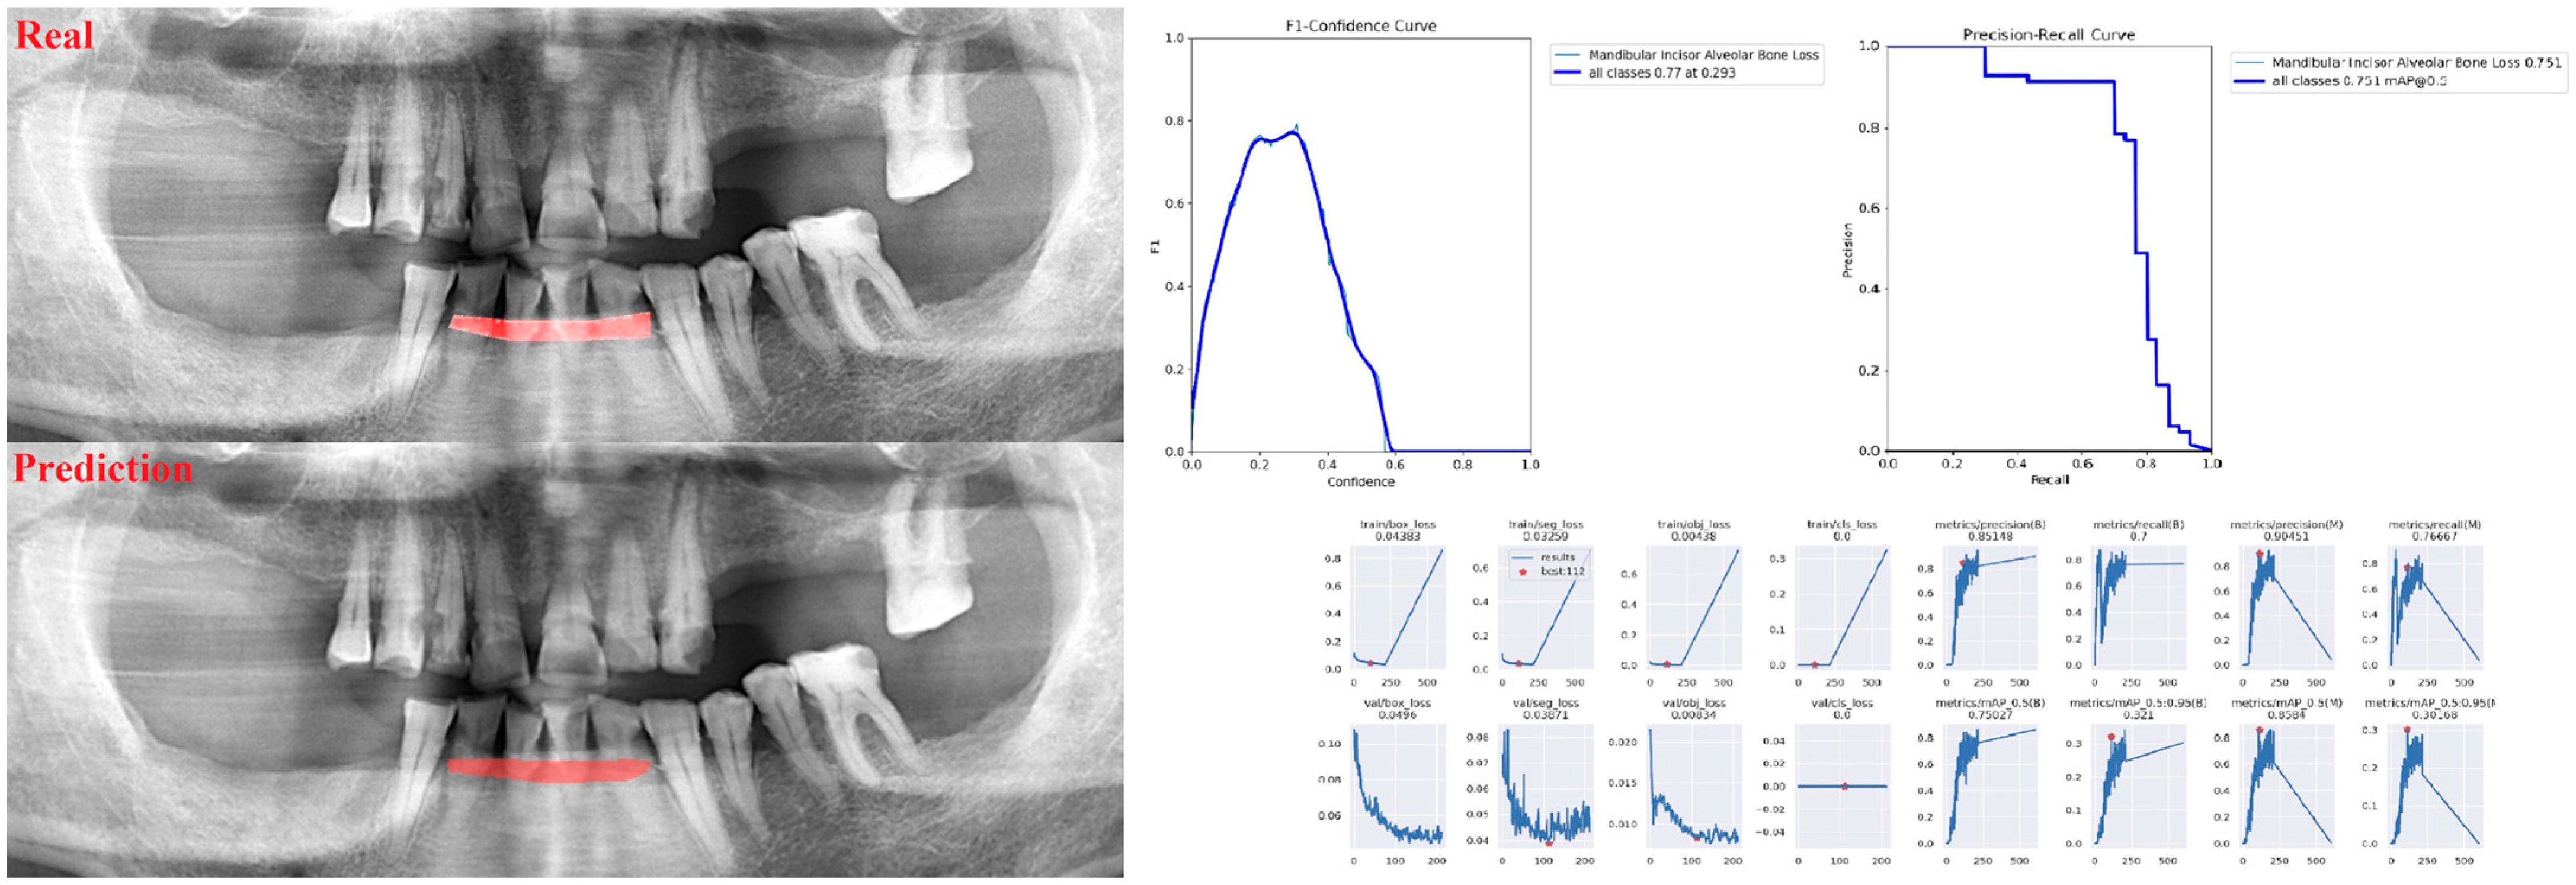

| Incisor ABL | 238 | 29 | 30 |

| Sensitivity | Precision | F1 Score | |

| Alveolar Bone Loss (ABL) | 0.75 | 0.76 | 0.76 |

| Mandibular | |||

| Incisor ABL | 0.83 | 0.89 | 0.86 |

| Canine ABL | 0.92 | 0.78 | 0.84 |

| Premolar ABL | 0.83 | 0.75 | 0.79 |

| Molar ABL | 0.85 | 0.73 | 0.79 |